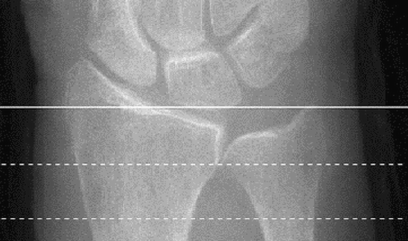

HR-pQCT scout view. The imaging procedure was defined to begin 9.5 mm proximal to the midline of the distal radius endplate (white line). The imaging range covered 9.0 mm (distance between the dotted lines)